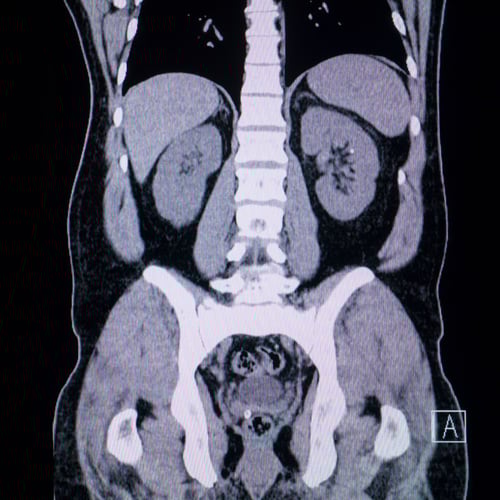

Using AI tools doesn’t make you an expert—any more than looking at your own CT scan makes you a radiologist. It just means you’re holding powerful instruments you may not fully understand.

Why Using AI Tools Doesn’t Make You an Expert (Any More Than Reading Your X‑Ray Makes You a Radiologist)

Imagine you log into your medical portal, open your MRI, zoom in and out, and carefully read the radiologist’s report. You can see the images. You can see the medical jargon. But you still don’t know how serious it is, what’s normal for your age, or what to do next. That’s the radiologist’s job, built on years of training, not a five‑minute scroll.

Owning a report is like owning imaging equipment: you still need someone who knows what they’re looking at and what to do about it.

The imaging analogy, one last time

AI in SEO is like imaging equipment in medicine:

- It’s powerful.

- It’s useful.

- It’s getting better.

But if you hand a patient their scan and say, “Good luck,” you’re not practicing medicine. You’re outsourcing outcomes to chance.

The same is true in digital marketing. If you hand your business an AI tool and call it a day, you’re hoping, not strategizing.